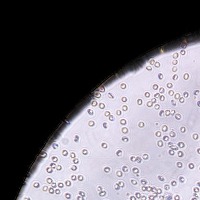

RBC Platelet v1 Computer Vision Project

Medical Diagnostic Tools: "RBC Platelet v1" can be integrated into diagnostic software systems to help physicians automatically detect and classify blood cells, aiding in faster disease diagnosis such as anemia, leukemia, or thrombocytopenia.

Biological Research: Researchers studying blood cells and diseases could use this model to automate cell identification and classification in their lab results, making for a more efficient research process.